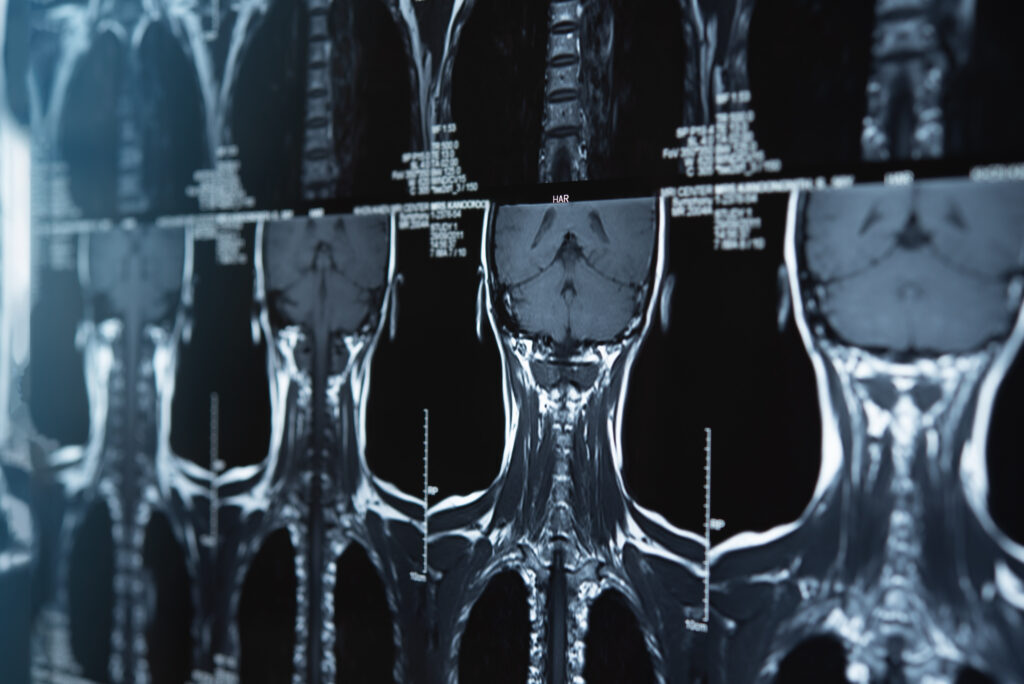

Below, find links to common radiology language that can help explain your results. Select the type of scan you had done to learn more.